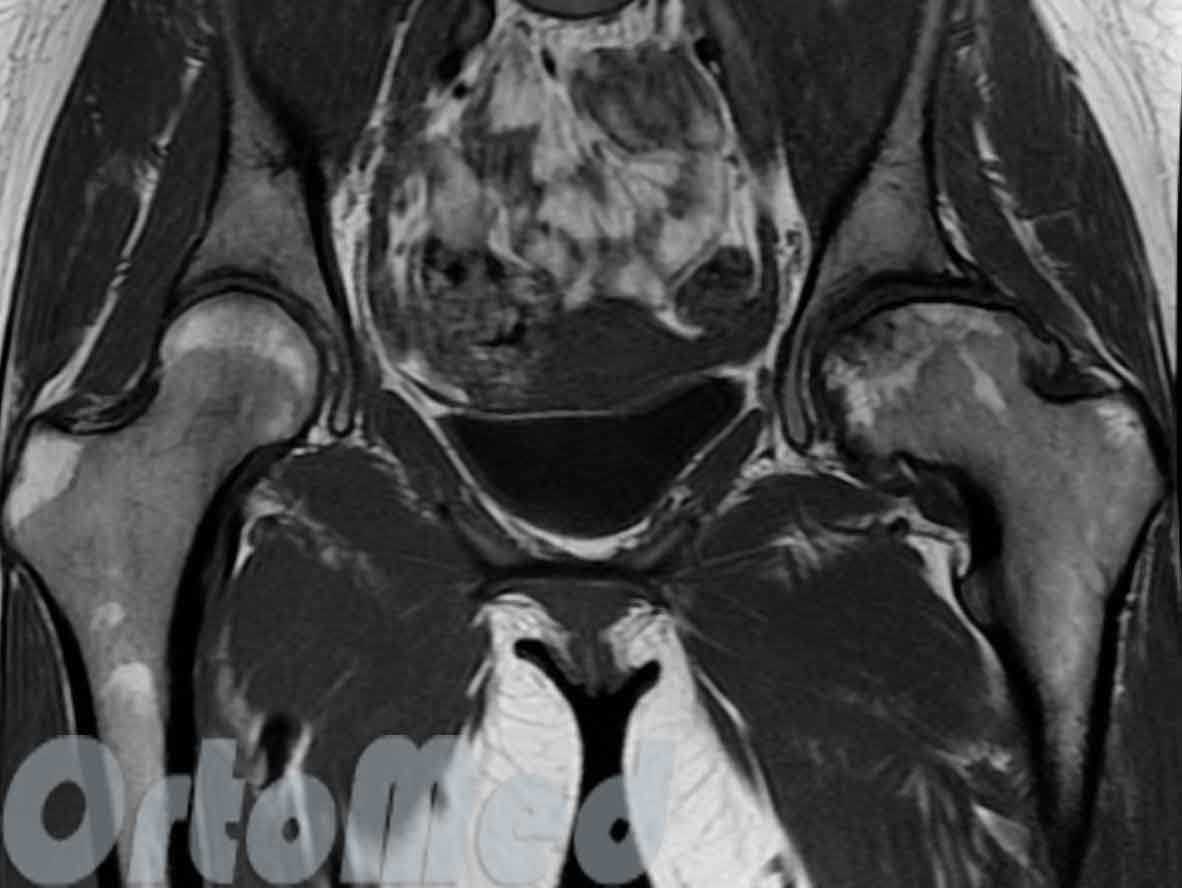

Магнитно-резонансная томография, на которой отчетливо видны очаги остеонекроза (гибели костной ткани) в головках обеих бедренных костей.

В данном случае показано тотальное эндопротезирование тазобедренного сустава (то есть замена его на искусственный).

На магнитно-резонансной томографии четко виден очаг разрушения в нагружаемой части головки левой бедренной кости